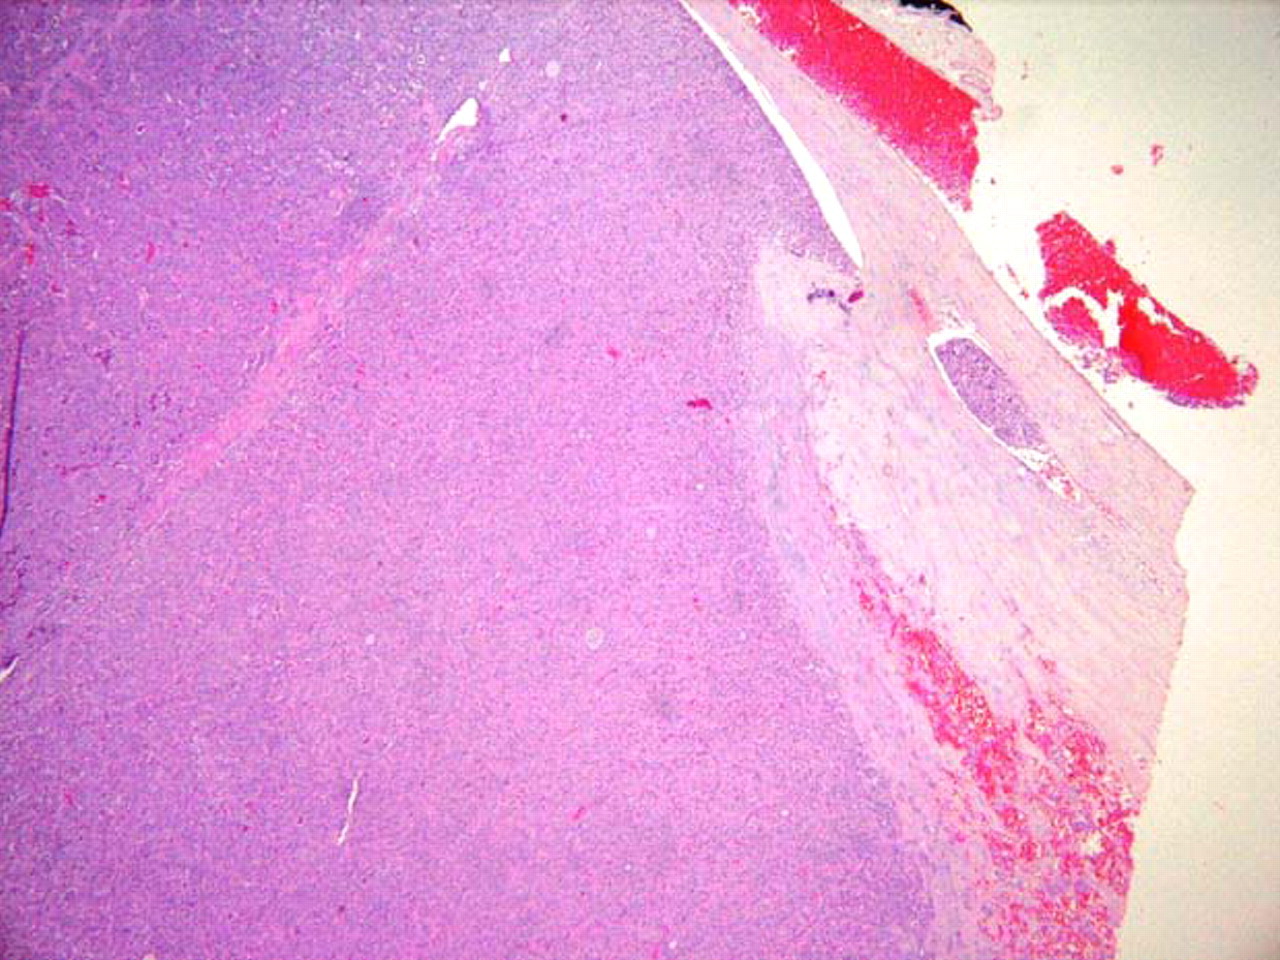

Histopathology of papillary carcinoma, thyroid: a psammoma body is visible (arrow)

CDC Image Library/Dr Edwin P. Ewing, Jr

See this image in context in the following section/s: